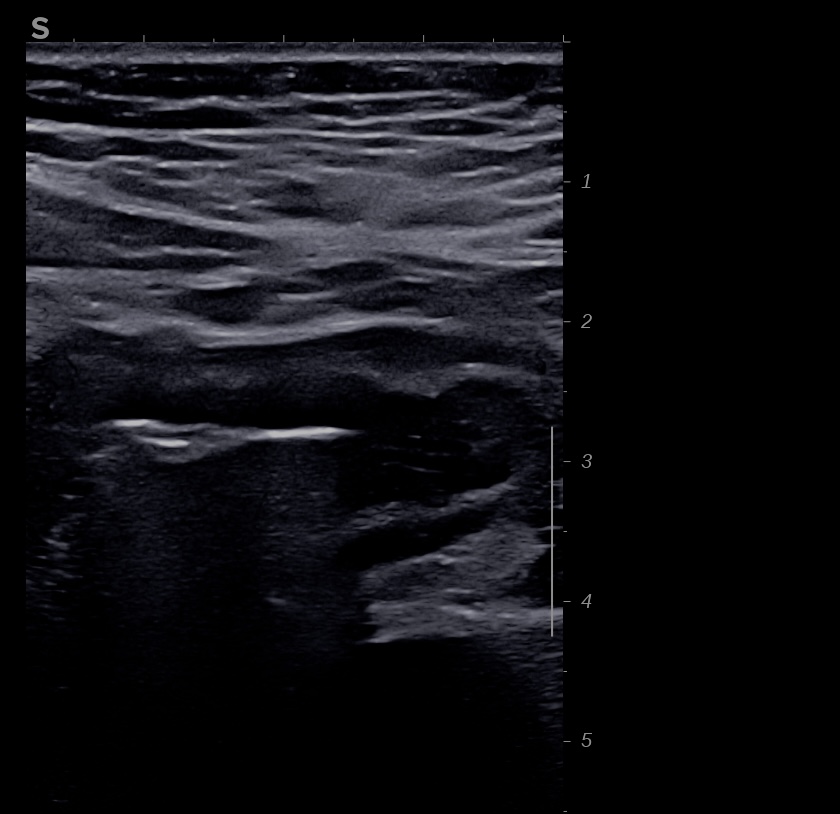

Là encore la paroi est très hypoéchogène, la structure en couches est par endroit totalement absente, ulcérations en surface, infiltration de la graisse, doppler intense, petites adénopathies périphériques.

Le rectum est bien vu avec la sonde basse fréquence la paroi atteint 10 mm à ce niveau.

Le score de Milan MUC est de (10 x1,4+2) = 16